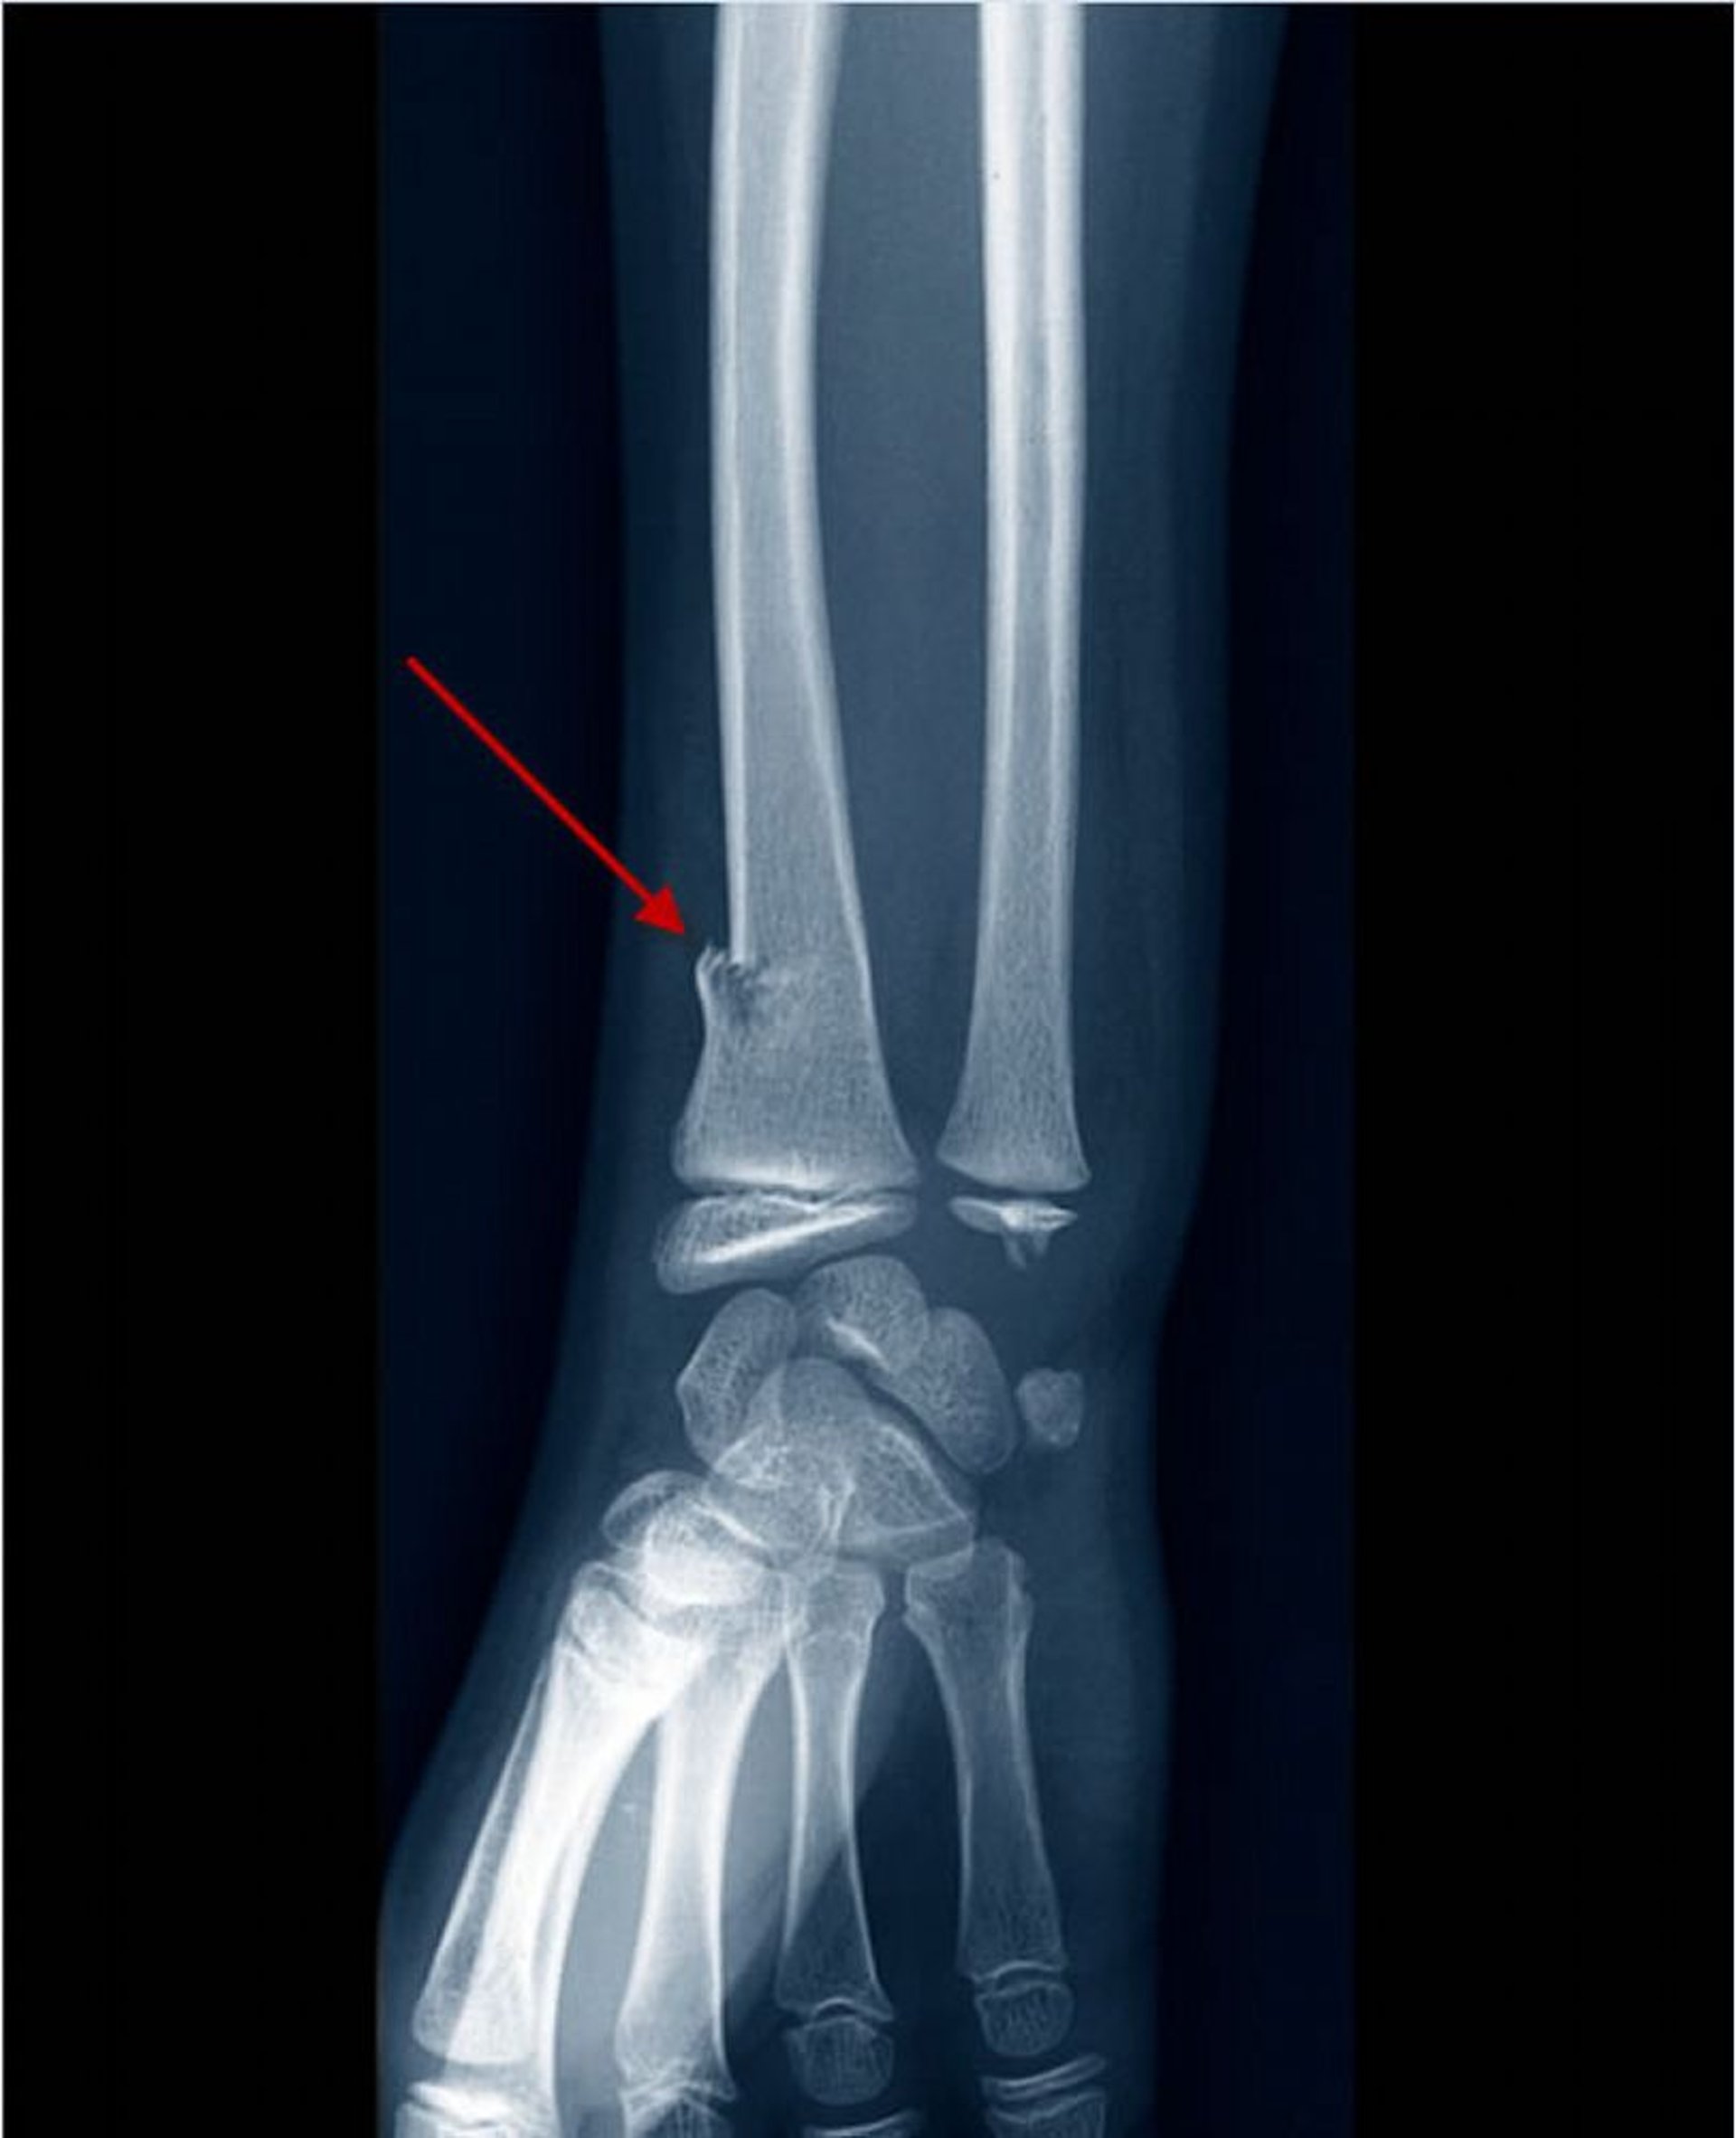

Fratura distal do rádio em galho verde

Essa radiografia mostra uma fratura distal do rádio em galho verde, visível como uma descontinuidade (deformidade) no aspecto radial do córtex (seta).